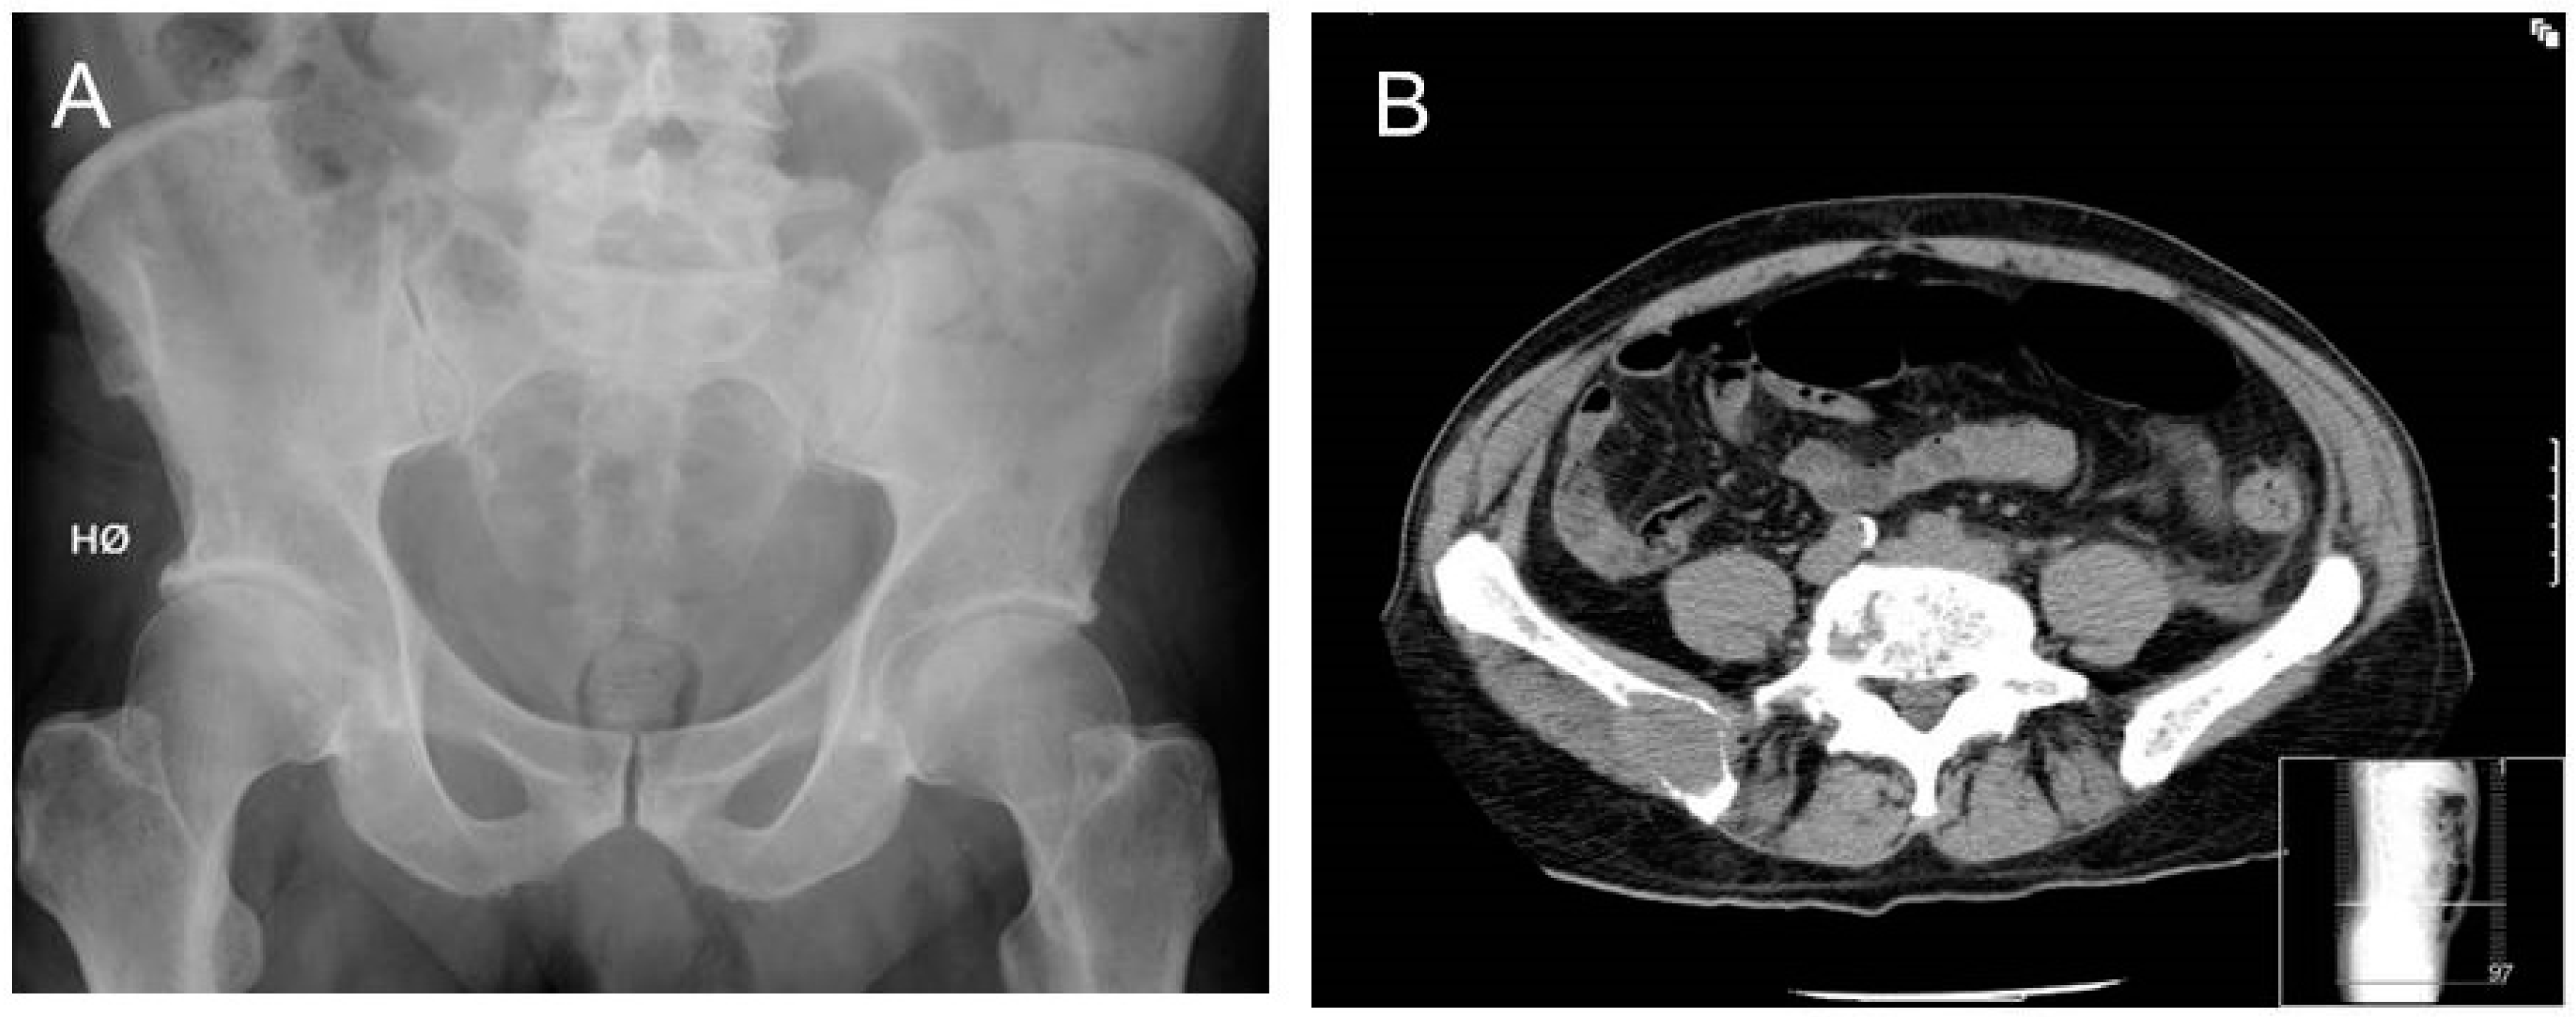

- Hinge, M.; Andersen, K.T.; Lund, T.; Jørgensen, H.B.; Holdgaard, P.C.; Ormstrup, T.E.; Østergaard, L.L.; Plesner, T. Baseline bone involvement in multiple myeloma—A prospectiv prospective comparison of conventional X-ray, low-dose computed tomography, and 18flourodeoxyglucose positron emission tomography in previously untreated patients. Haematologica 2016, 101, e415–e418. [Google Scholar] [CrossRef] [PubMed]

- Hillengass, J.; Moulopoulos, L.A.; Delorme, S.; Koutoulidis, V.; Mosebach, J.; Hielscher, T.; Drake, M.; Rajkumar, S.V.; Oestergaard, B.; Abildgaard, N.; et al. Whole-body computed tomography versus conventional skeletal survey in patients with multiple myeloma: A study of the International Myeloma Working Group. Blood Cancer J. 2017, 7, e599. [Google Scholar] [CrossRef] [PubMed]